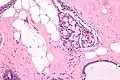

Collagenous spherulosis is characterized by a tubular/cribriform architecture with intratubular eosinophilic material that classically is arranged like the spokes of a wheel ("radial spikes"). There is usually no mitotic activity, and two cells populations (epithelial & myoepithelial) are present, like in benign breast glands.

The lesions are typically small (less than 50 spherules per lesion, less than 100 micrometers in size) and may be multifocal.

Intermed. mag. High mag.

High mag.